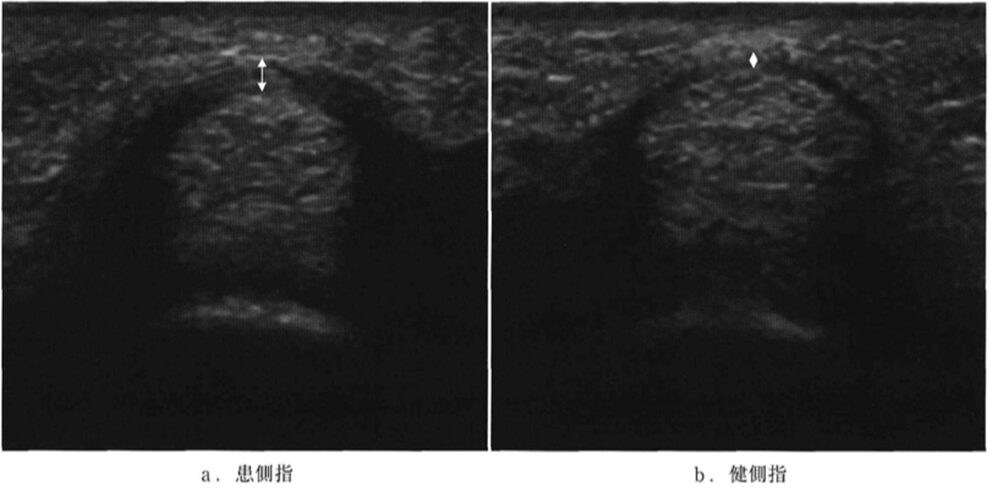

ばね指の診断においてエコーを用いると、炎症を起こして分厚くなった腱や腱鞘の状態、腱の滑走が悪い様子、周辺の血流が増加している様子などを、患者さんご自身の目で直接確認することができます。これにより、診断の正確性が格段に向上するだけでなく、ご自身の身体の中で何が起きているのかを深く理解し、納得して治療に進んでいただくことができます。

a:ばね指のエコー所見:腱鞘(黒い部分)が肥厚している

b:健常者のエコー所見:腱鞘(黒い部分)が薄い

出典:亀山真. 2012. 狭窄性屈筋腱腱鞘炎の超音波診断. MB Orthop. 25(8): 53-59.